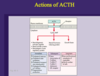

ACTH-dependent Cushing’s Syndrome

High ACTH

- Cushing’s Disease (pituitary tumor) - most common

- ectomic ACTH (carcinoid tumor)

Rare: ectopic CRH secretion